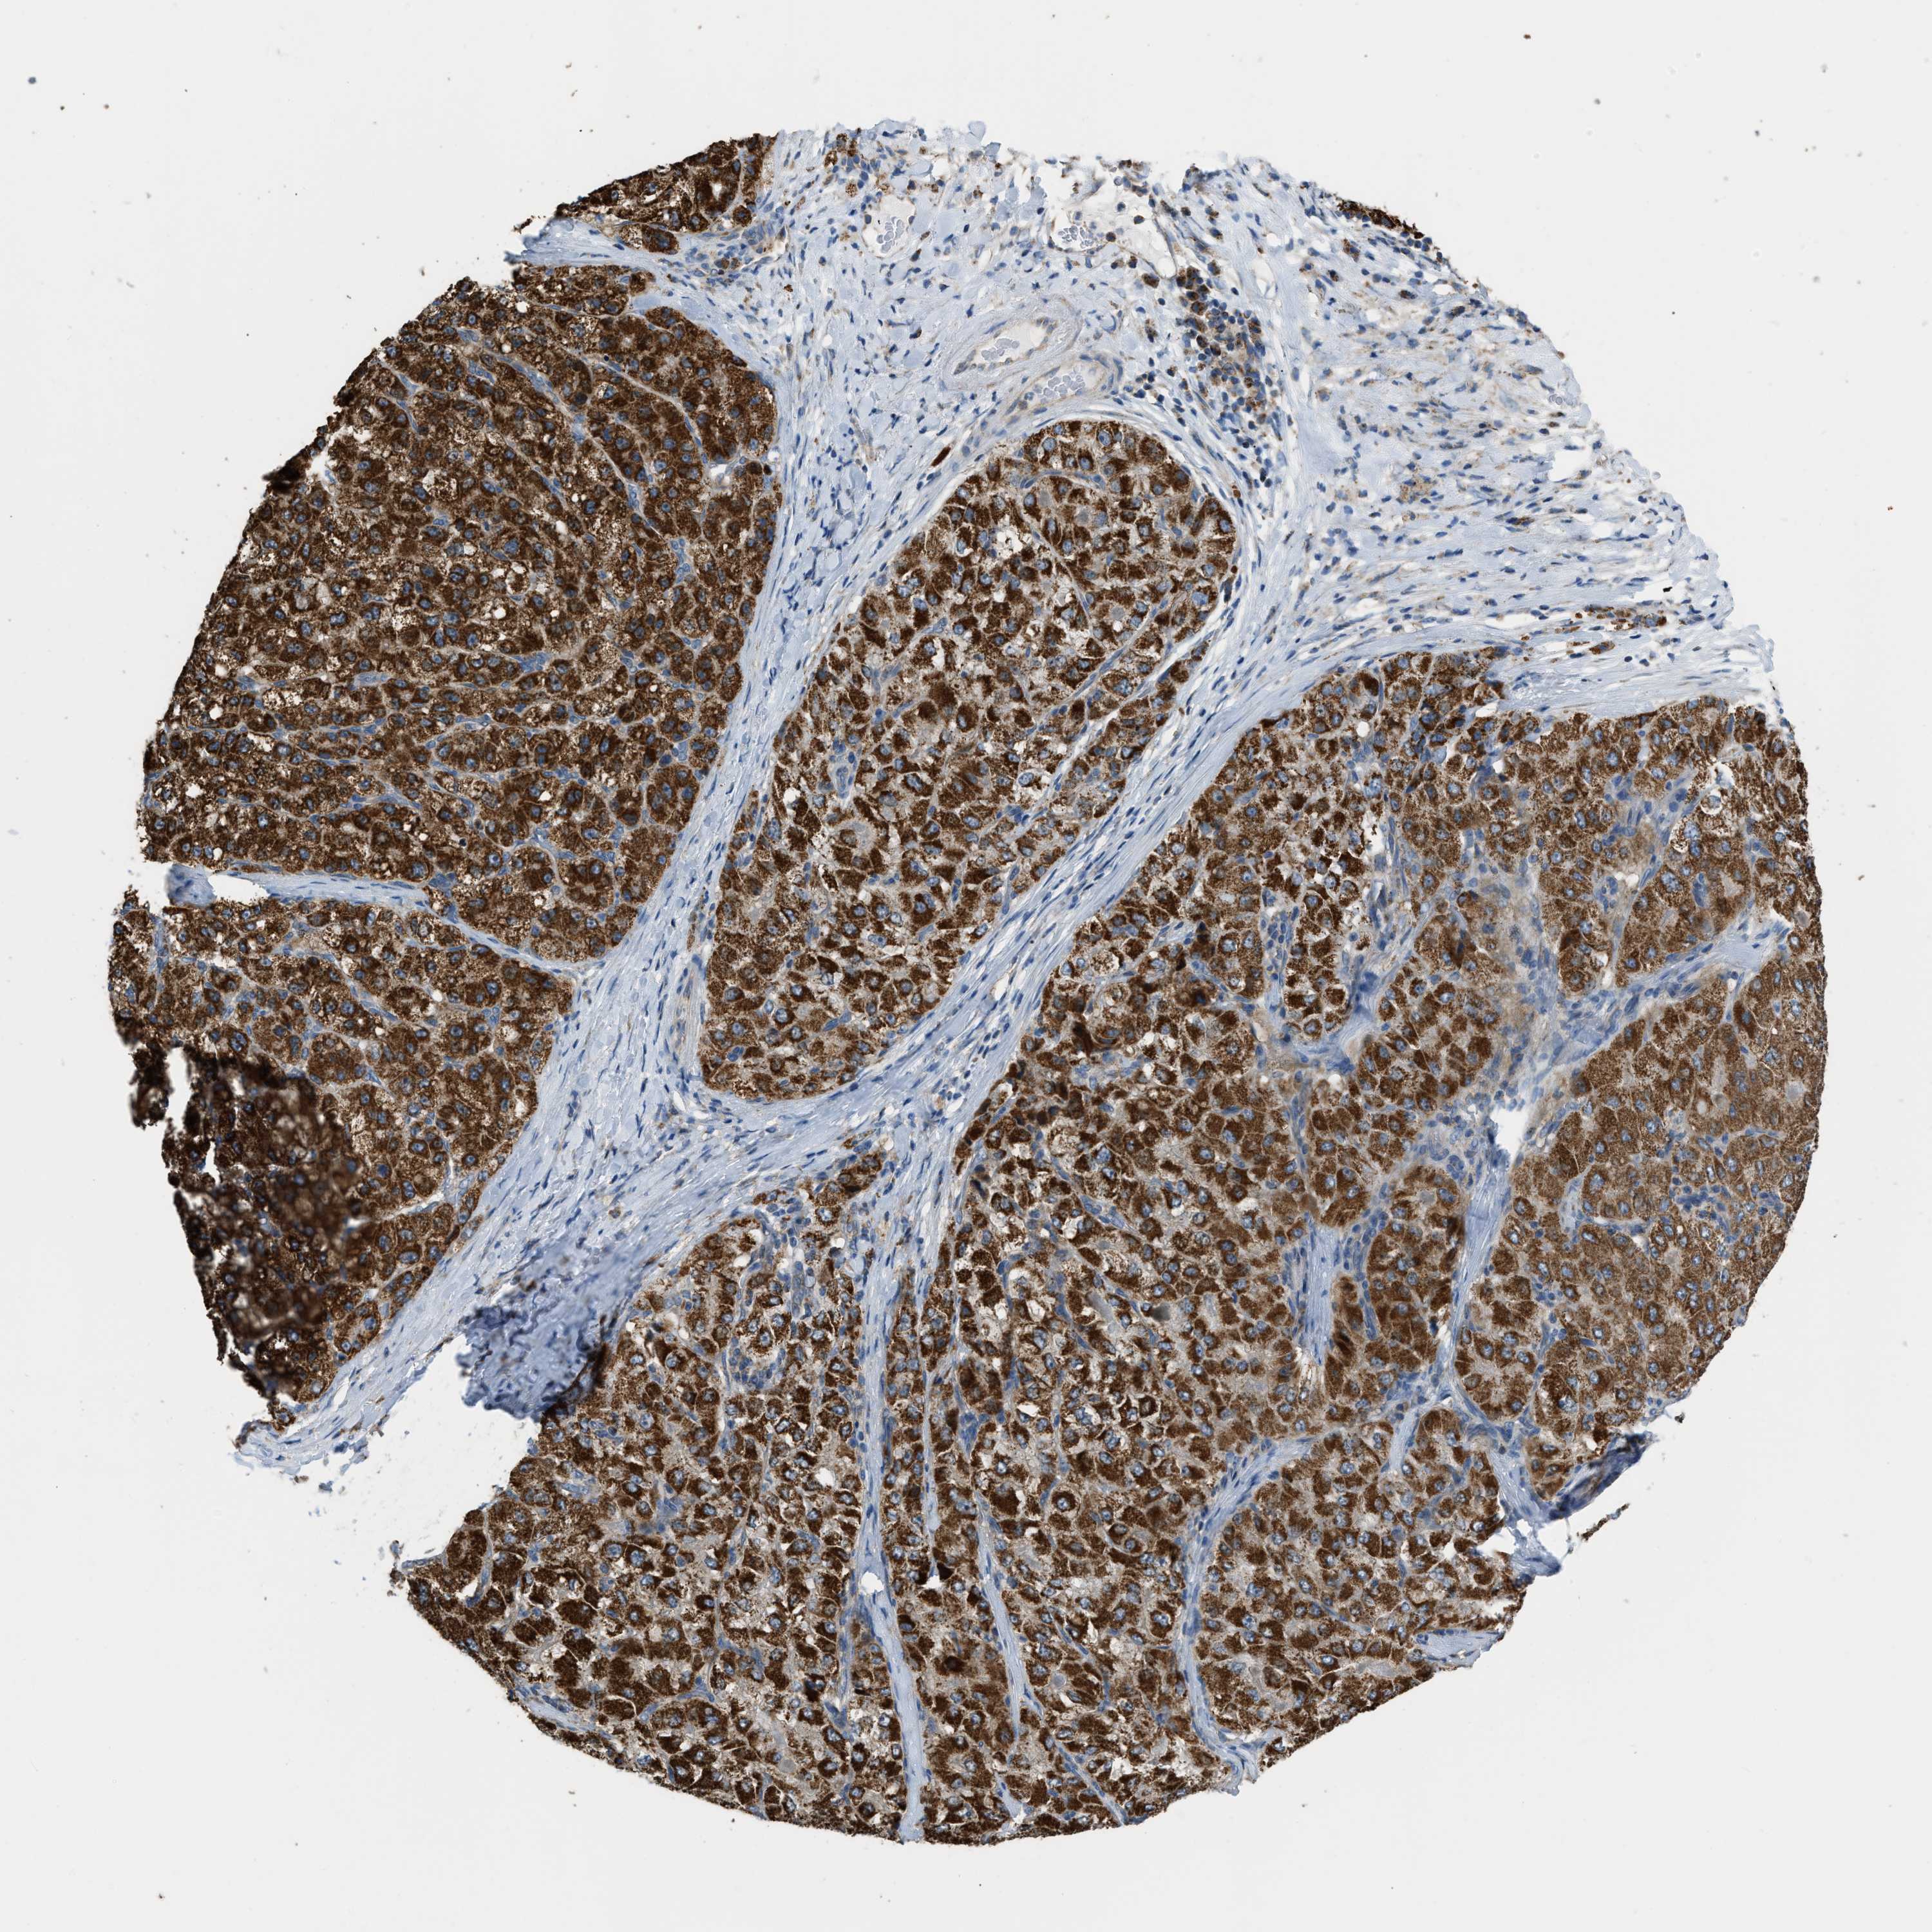

LIVER CANCER - Protein expressioni

A mouse-over function shows sample information and annotation data. Click on an image to view it in a full screen mode. Samples can be filtered based on level of antibody staining by selecting one or several of the following categories: high, medium, low and not detected. The assay and annotation is described here.

Antibody stainingi

Antibody staining in the annotated cell types in the current human tissue is reported as not detected, low, medium, or high, based on conventional immunohistochemistry profiling in selected tissues. This score is based on the combination of the staining intensity and fraction of stained cells.

Each image is clickable and will lead to virtual microscopy that enables deeper exploration of all samples and also displays staining intensity scores, fraction scores and subcellular localization as well as patient and tissue information for each sample.

Antibody HPA018910

Antibody HPA018921

Antibody HPA018923

Staining

High

Medium

Low

Not detected

Intensity

Strong

Moderate

Weak

Negative

Quantity

>75%

75%-25%

<25%

None

Location

Nuclear

Cytoplasmic/membranous

Cytoplasmic/membranous,nuclear

Cholangiocarcinoma

Carcinoma, Hepatocellular, NOS